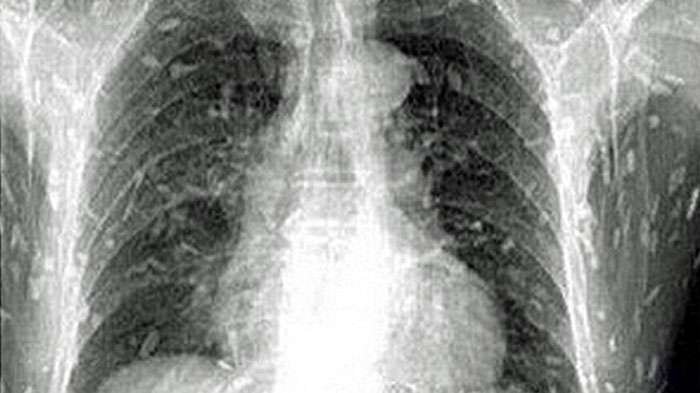

Cacing pita di seluruh tubuh seorang pria

Setelah dilakukan pemeriksaan dan scan hasilnya sangat mengerikan.

Terdapat cacaing pita hampir di seluruh tubuh pria ini.

Nah, akibat terinfeksi cacing pita, pria ini dirawat di rsebuah rumah sakit di bagian Timur Tiongkok.